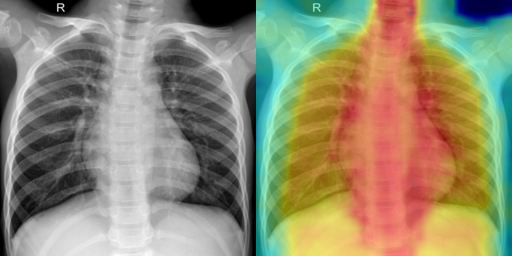

To illustrate failure cases of an anomaly detection model for bacterial pneumonia, we illustrated the heatmaps in Fig. 7. In the first example, the model misclassifies normal anatomical structures such as the cardiac border and diaphragm as abnormal regions, resulting in a false positive. In the second example, it fails to detect subtle and diffuse pulmonary opacities, leading to a false negative. These errors highlight the model’s sensitivity to normal intensity variations and its limited ability to recognize low-contrast infections.